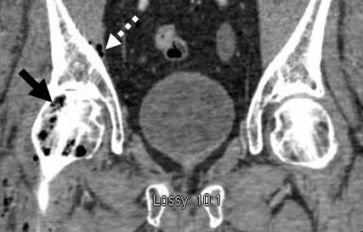

A CT scan of the abdomen and pelvis revealed multiple foci of gas throughout the right femoral head (Figures 1 and 2, black arrows); gas extending along the right iliacus muscle (Figures 1 and 2, dashed white arrows) and an air-fluid level within the gallbladder lumen (Figure 1, solid white arrow) with peripheral gas in the wall (Figure 3, solid white arrow). Culture of the hip bone was positive for Clostridium perfringens and confirmed a diagnosis of emphysematous cholecystitis (EC) caused by C perfringens with spread to the right hip.

Figure 1. Sagittal image